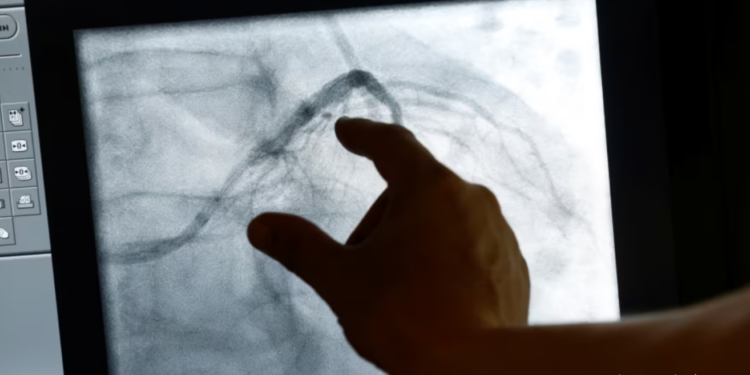

Studiuesit e inxhinierisë biomjekësore në Universitetin Johns Hopkins po punojnë për të transformuar kujdesin shëndetësor për pacientët me sëmundje të zemrës.

Ata tani mund të krijojnë një kopje dixhitale të zemrës së një pacienti dhe me ndihmën e inteligjencës artificiale mund të bëjnë parashikime më të sakta mbi rreziqet me të cilat përballen pacientët.

“Ne bëjmë imazhe me rezonancë magnetike të zemrës dhe më pas mund të kombinojmë të gjitha të dhënat klinike që njihen për pacientin. Kjo kombinohet me analizën e mbijetesës dhe ne mund të parashikojmë për një periudhë mbi 10 vjeçare nivelin e rrezikut të një pacienti nga një vdekje e papritur kardiake.”

Ndryshe nga imazhet e segmentuara që përdoren më shpesh sot, profesorja Natalia Trayanova thotë se imazhet e plota të zemrës,

ofrojnë parashikime më të sakta për pacientët që mund të kenë nevojë për defibrilatorë.

“Ne kemi algoritme që ofrojnë analiza më të hollësishme dhe një pasqyrë më të mire të gjendjes shëndetësore të pacientit”, thotë profesorja Trayanova.